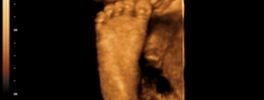

4D Sonography-Foetal Foot